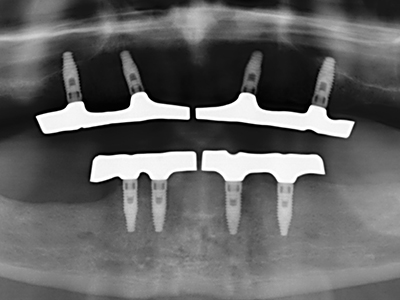

Come dimostrato in passato, pressoché qualsiasi procedura chirurgica che interessa il tessuto osseo rappresenta una possibile indicazione per la piezochirurgia. Quindi, per la preparazione del segmento mobile nella distrazione osteogenetica (figg. 23-25) e nell'osteotomia con tecnica a sandwich si utilizzano appositi raccordi per non danneggiare l'apporto sanguigno alla sezione della cresta, elemento essenziale per la corretta esecuzione di entrambe le tecniche (Gonzalez-Garcia, Diniz-Freitas et al. 2008).

Per la rimozione di un impianto, è possibile preparare una copertura dell'osso vestibolare da sostituire dopo la rimozione della vite dell'impianto, per conservare il contorno della cresta alveolare.

Esistono ulteriori applicazioni nella chirurgia sinusale. È possibile rimuovere patogeni e corpi estranei dal seno dopo la preparazione concentrica di una copertura ossea generalmente di forma trapezoidale nella parete anteriore del seno. La copertura ossea viene riposizionata al termine della fase operatoria nella zona intra-antrale e fissata con cunei o suture adattive per prevenirne il distacco.